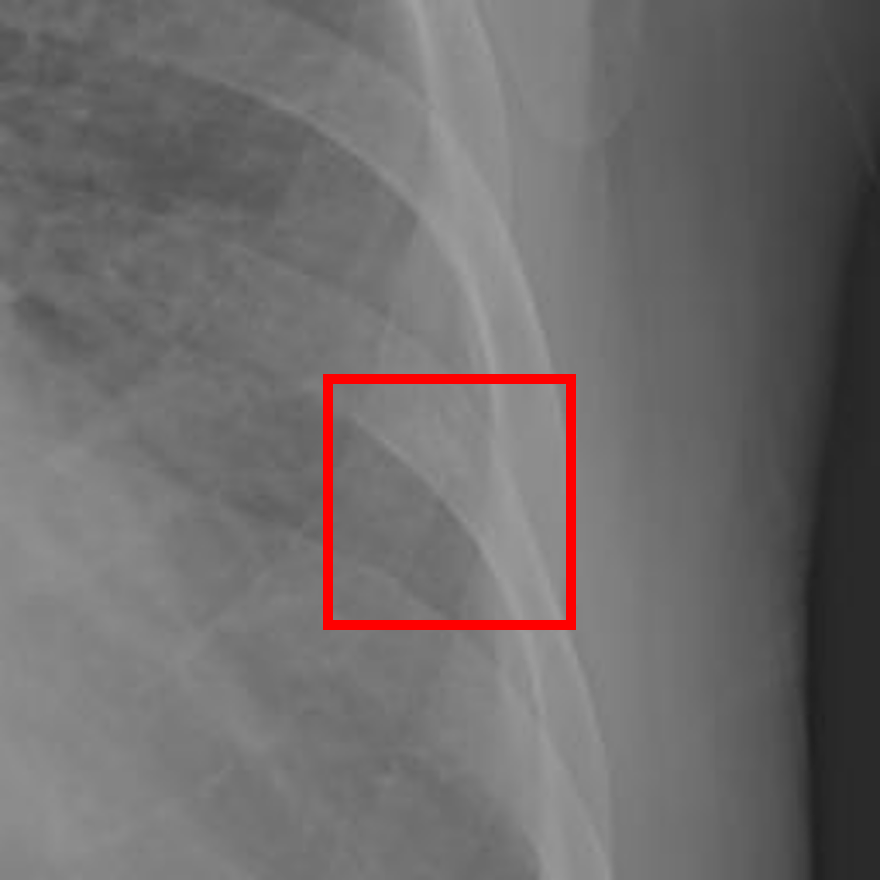

Refer to caption

(a) Healthy(1)

(b) NODE21

(c) Healthy(2)

(d) VinDr-CXR

Figure 5: Grad-CAM-based saliency maps illustrating model interpretability across datasets. Top row: Examples from NODE21 showing baseline (a) and curriculum-trained (b) models. Bottom row: Examples from VinDr-CXR demonstrating consistent attention patterns (c, d).

Grad-CAM visualizations showed that curriculum-trained models consistently focused on anatomically meaningful lung regions near nodules (Figure 5b), while baseline models activated broader, clinically irrelevant regions (Figure 5a). Similar attention patterns were observed across NODE21 and VinDr-CXR examples (Figure 5c,d), supporting interpretability and robustness.